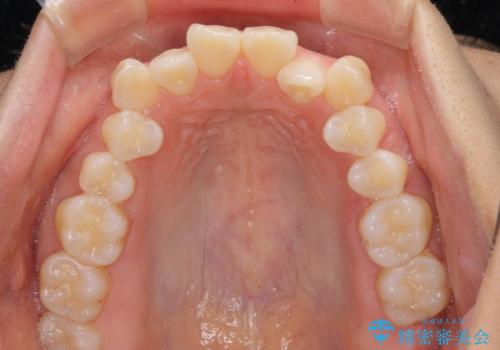

- 前歯のデコボコと口元の突出感を気にして来院された患者様です。

非抜歯矯正ではデコボコを解消することでより口元が突出してしまうため、上下左右の小臼歯4本の抜歯を行い、ワイヤー装置による矯正治療を行うこととしました。

もう少し口元の突出感を改善したかったのですが、舌の突出癖が影響し下顎前歯が唇側に押させる仕上がりとなりました。